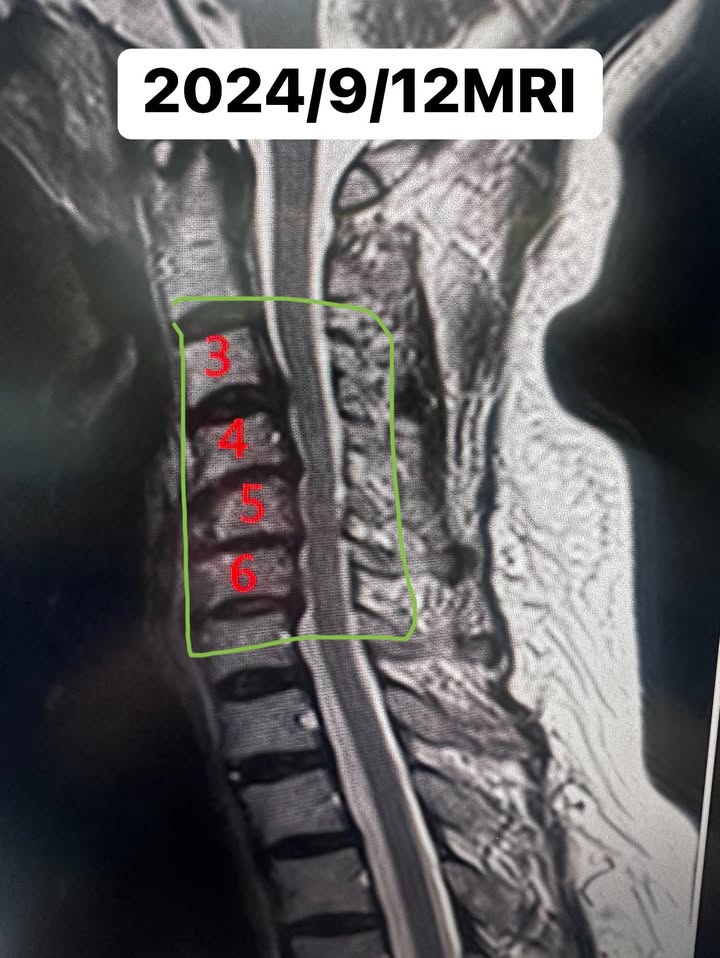

2024/9月12日,林阿姨懷著一絲期待,來到了我們的門診。那天,她雙手輕輕顫抖,語氣卻堅定地說:「徐醫師!我還想為家人煮飯,我不想成為他們的負擔。」我們醫療團隊被她的話深深觸動,決定盡全力幫助她。經過詳細問診與檢查,我們立即安排了核磁共振(MRI)。檢查結果並不樂觀——她的頸椎壓迫範圍涵蓋三節,其中三四節跟五、第六節最為嚴重,不僅滑脫,還合併椎間盤突出及神經孔狹窄。這些問題如同一道道枷鎖,牢牢束縛著她的生活。